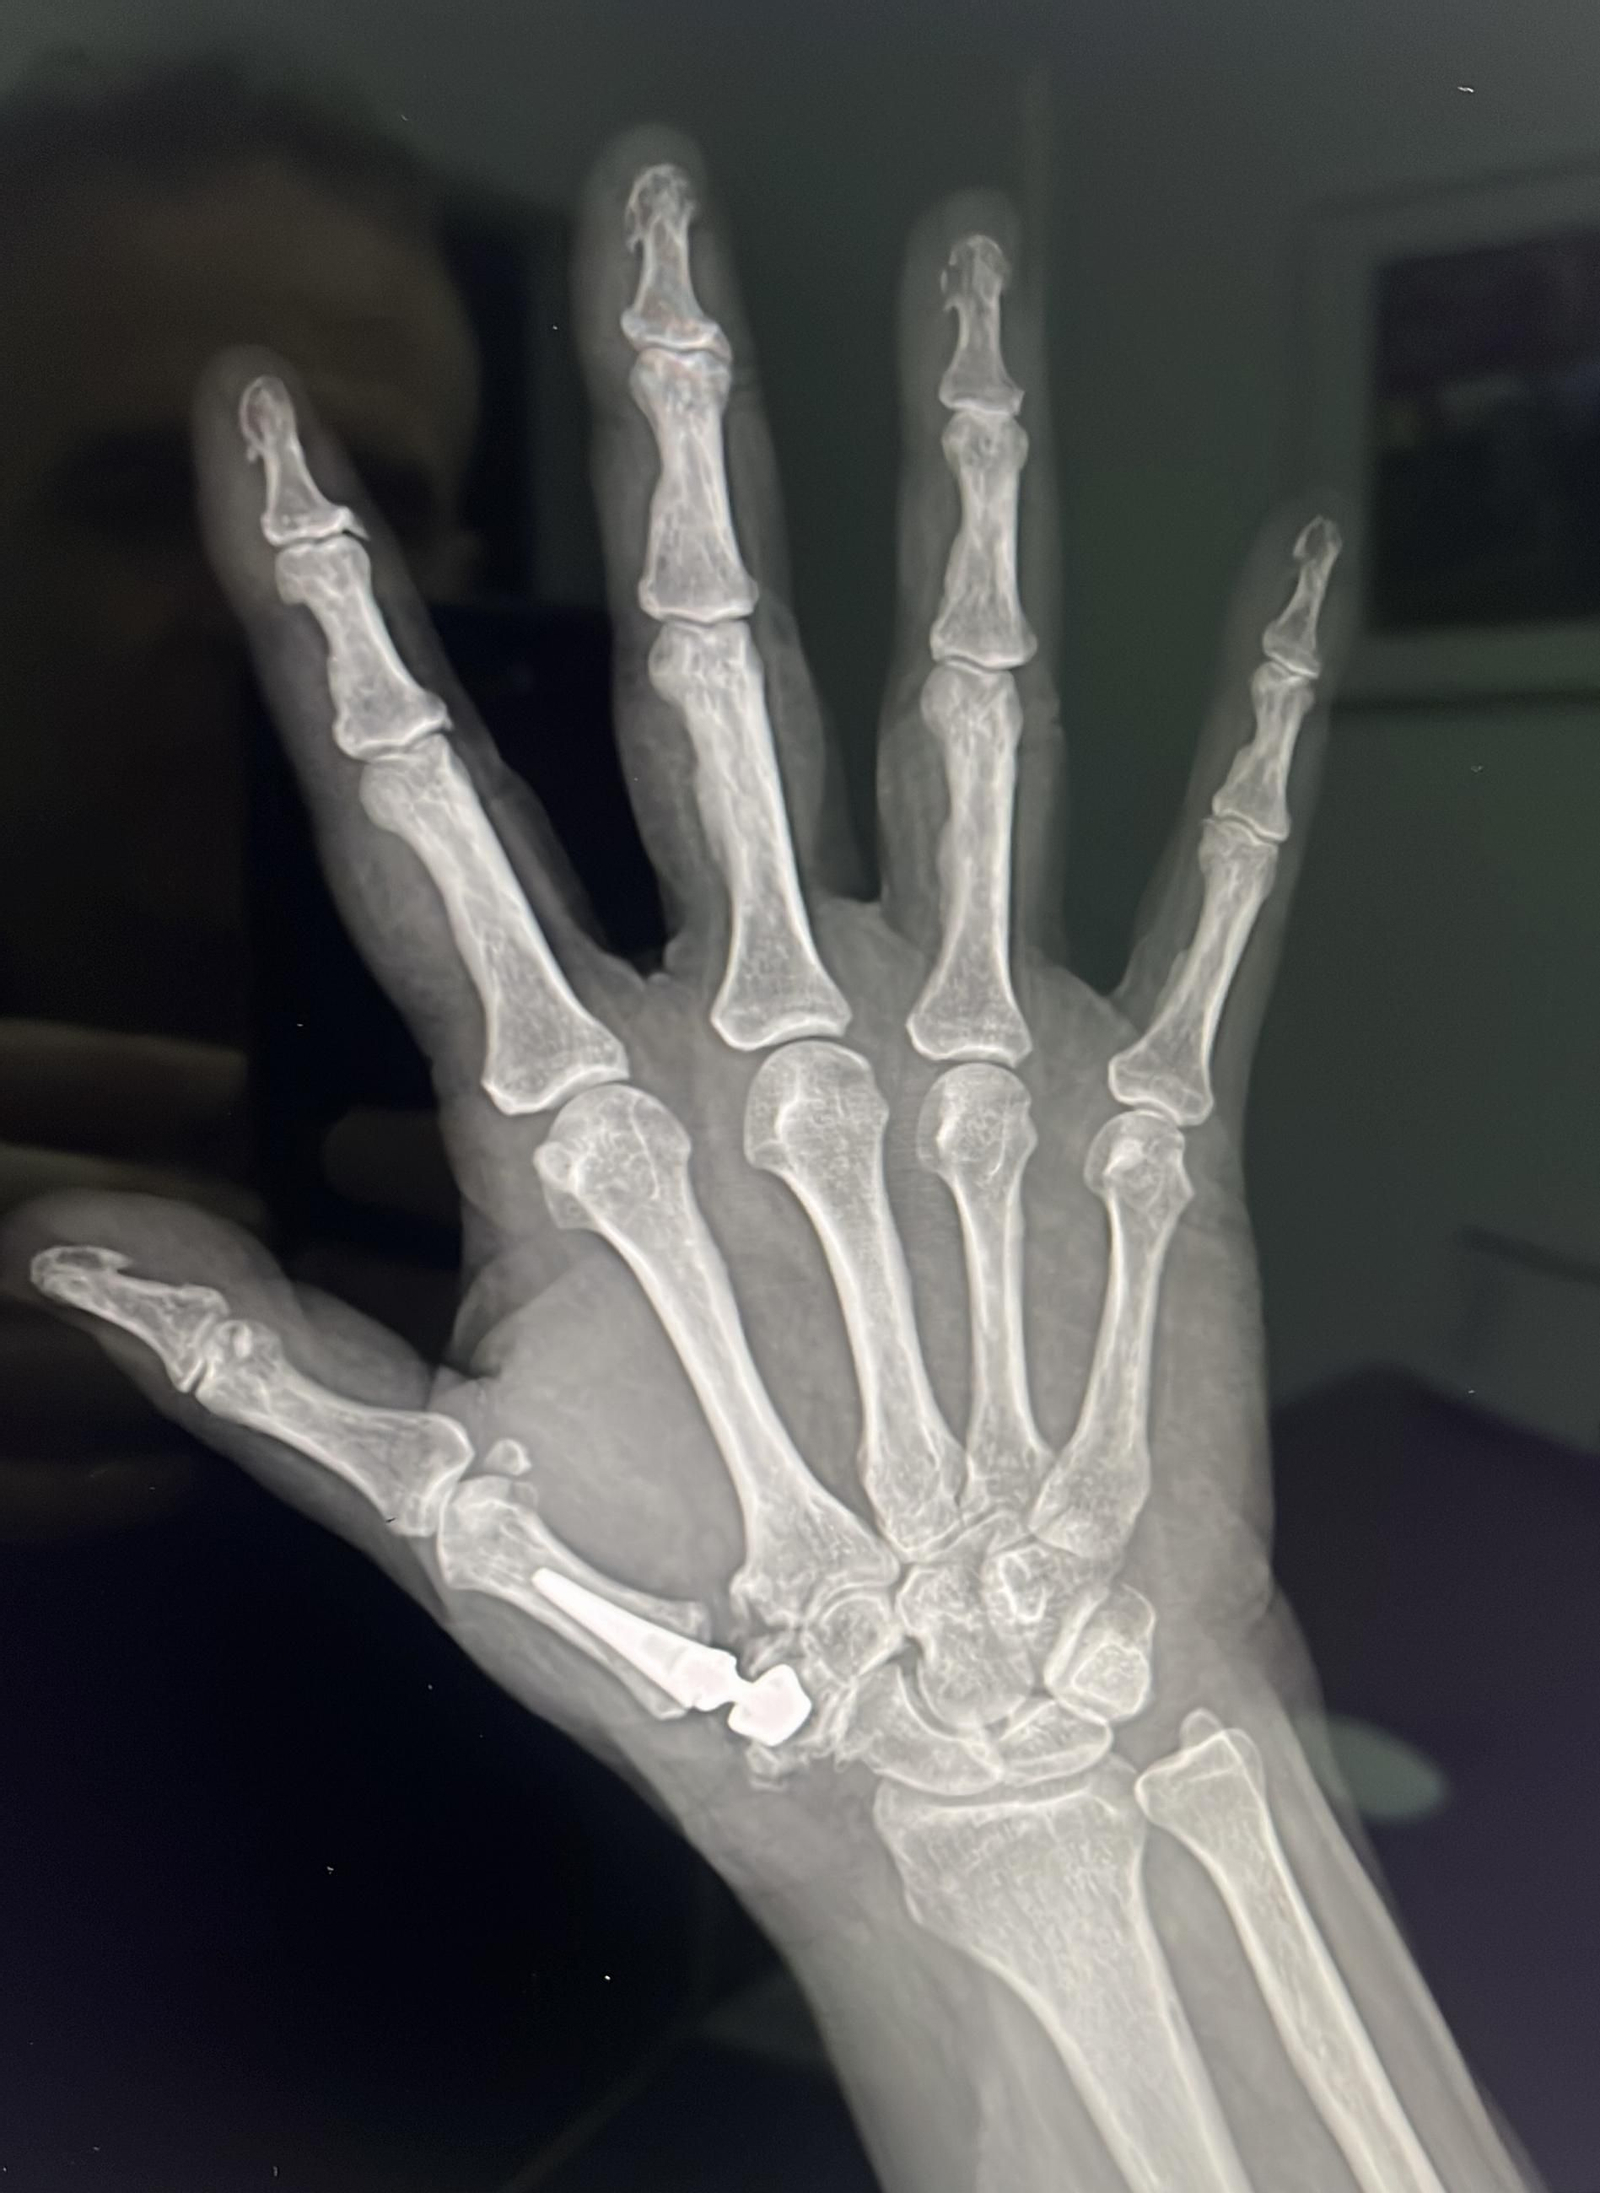

Radiografía en la que se observa la implantación de una prótesis trapeciometacarpiana como la que se ha tenido que usar con Rafa Nadal.

Radiografía en la que se observa la implantación de una prótesis trapeciometacarpiana como la que se ha tenido que usar con Rafa Nadal. / D.A.

-Artroplastia total: Consiste en colocar una prótesis trapeciometacarpiana. El aspecto es similar a las que tienen las de cadera: hay un vástago que se coloca dentro del primer dedo, una cabeza esférica que articula sobre una cúpula llamada acetábulo que se coloca en el trapecio. La movilidad es completa y la fuerza también. Es la intervención que se ha realizado Nadal. De esta forma, ni pierde movilidad ni prácticamente fuerza, sobre todo de agarre. Esa articulación se ha desgastado debido al agarre de la raqueta y los golpeos todos estos años.